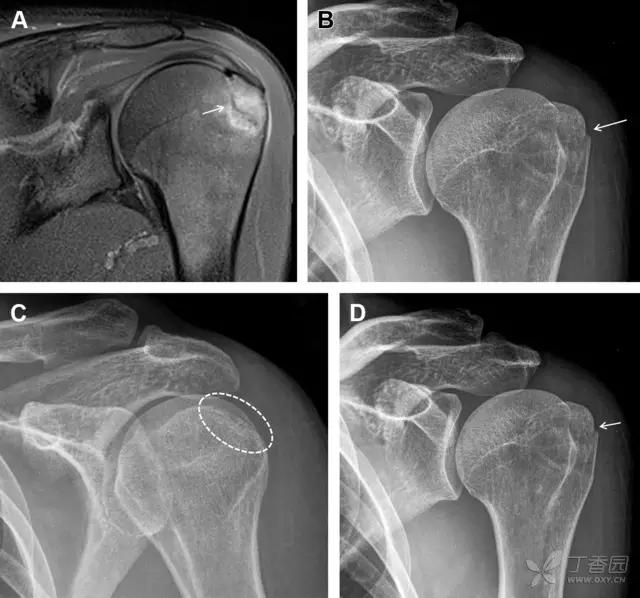

23 单纯肱骨大结节骨折

与其它肱骨近端骨折不同,单纯肱骨大结节骨折常发生于年轻人。肱骨大结节骨折常由撞击或剪切/撕脱损伤所致:

撞击包括直接撞击、肩峰撞击、上关节盂撞击(极度外展时);

剪切/撕脱损伤常发生于肩关节前脱位。

在常规前后位片上,大结节与肱骨头重叠,骨折不易发现,外旋位前后位片有助于诊断。

图 1 大结节骨折。(A)脂肪抑制序列斜冠状位 MRI,显示肱骨大结节线性骨折无移位(箭头)与周围骨水肿;(B)外旋位前后位(AP)片,证实大结节骨折(箭头),典型的骨折愈合过程中的骨吸收表现;(C、D)初诊时内旋位、外旋位前后位片,初诊时漏诊,仔细回顾影像,内旋伞下可见双密度影(椭圆),骨皮质中断(箭头)